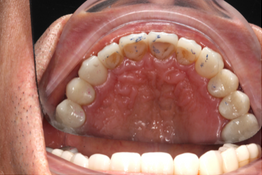

Mr NK, a 52-year-old male, presented with concerns of gradually shortening teeth and sensitivity to cold drinks. He also reported feeling self-conscious about his smile in photos. He is medically fit and has been using a night guard for his sleep-related grinding habit for the past year. Clinical examination revealed moderately worn dentition from erosion and attrition, along with mild crowding of the lower anterior incisors.

Intra-Oral Pictures (Before)

- Erosion severity: ACE Class Class III

- Reduced occlusal vertical dimension

- Mild crowding of lower anterior teeth